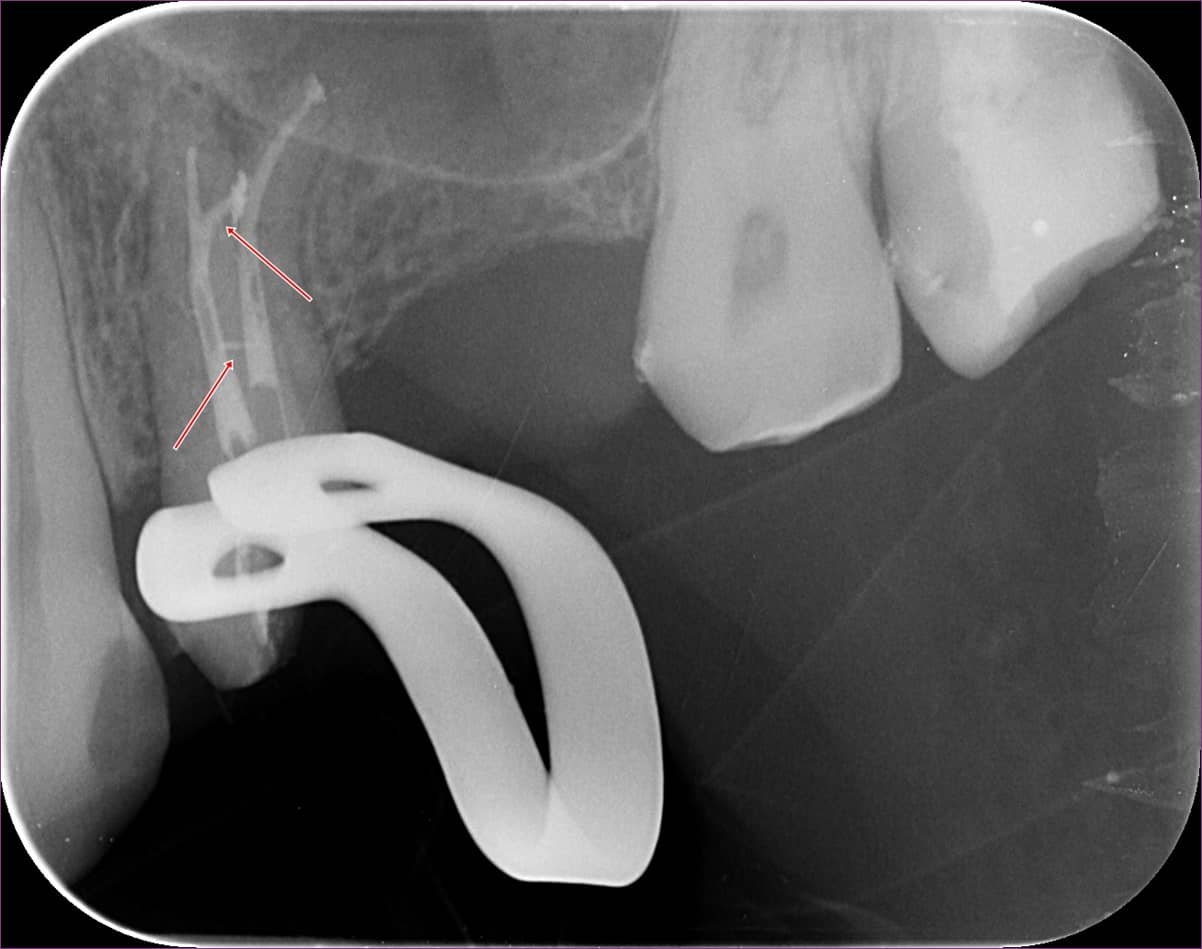

Közvetlenül a gyökértömés előtt a majdani gyökértömő „pálcikákkal” készült röntgenfelvételen ellenőriztük, valóban jó helyen vagyunk-e, és az elektromos bemérő készülékünk segítségével jó hosszokat sikerült-e megállapítanunk.

A felvételen egyenesebbnek látszó gyökérben rövidebbnek tűnik a hossz a röntgenen látható véghez képest, azonban itt nem a gyökércsúcson van a kijárat, hanem a gyökér oldalán.

(A szalagszerű képlet a kofferdam-kapocs árnyéka.)

A gyökérkezelés menete szerint ezután kerül sor a gyökértömésre. A gyökértömésről készült felvételen nagyszerűen látszik egy ilyen oldalcsatorna teljes feltelítődése: ezt nyilakkal jelöltük.